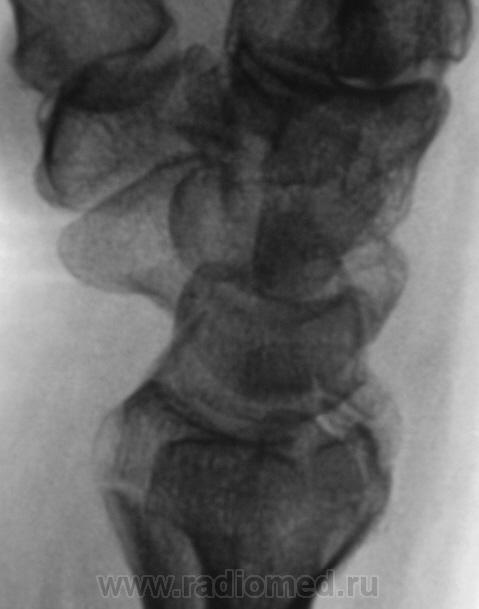

Травма.

Вот еще одна непонятность.

А линия просветления в метаэпифизе луча?

Контур нечеткий, склероз и т.д.-на перелом не схоже. А действительно локальная болезненность в латер. лодыжке?

Да, болезненность есть, клинически хирурги - за перелом.

Краевой перелом Наружной лодыжки